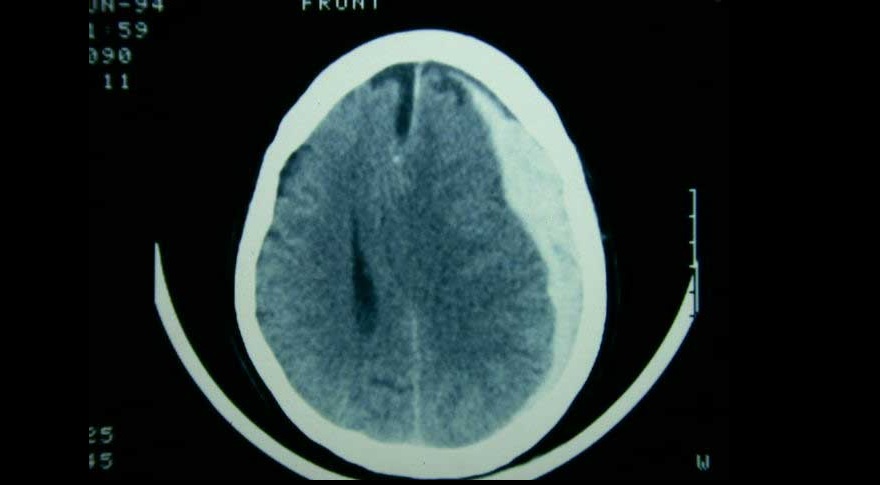

Tres ensayos clínicos exploran la utilidad de la embolización de esta arteria en el manejo del hematoma subdural subagudo o crónico, con miras a reducir la tasa de recurrencias y la necesidad de nuevas intervenciones. New England Journal of Medicine, 20 de noviembre de 2024.

El tratamiento de pacientes con hematoma subdural agudo difiere según el centro de tratamiento, debido a la variación en el abordaje preferido. Una estrategia de tratamiento que prefirió un enfoque agresivo de evacuación quirúrgica aguda sobre el tratamiento conservador inicial no se asoció con un mejor resultado funcional. The Lancet Neurology, 5 de mayo de 2022.

Un ensayo clínico mostró que el corticoide se asoció a peores resultados clínicos a los seis meses en comparación con placebo, pero con menor cantidad reoperaciones. New England Journal of Medicine, 16 de diciembre de 2020.

El uso creciente de fármacos anticoagulantes y antiagregantes se asocia a un aumento de hematomas subdurales, especialmente en los mayores de 75 años. La combinación de antagonistas de vitamina K con antiplaquetarios potencia el riesgo. JAMA, 28 de febrero de 2017